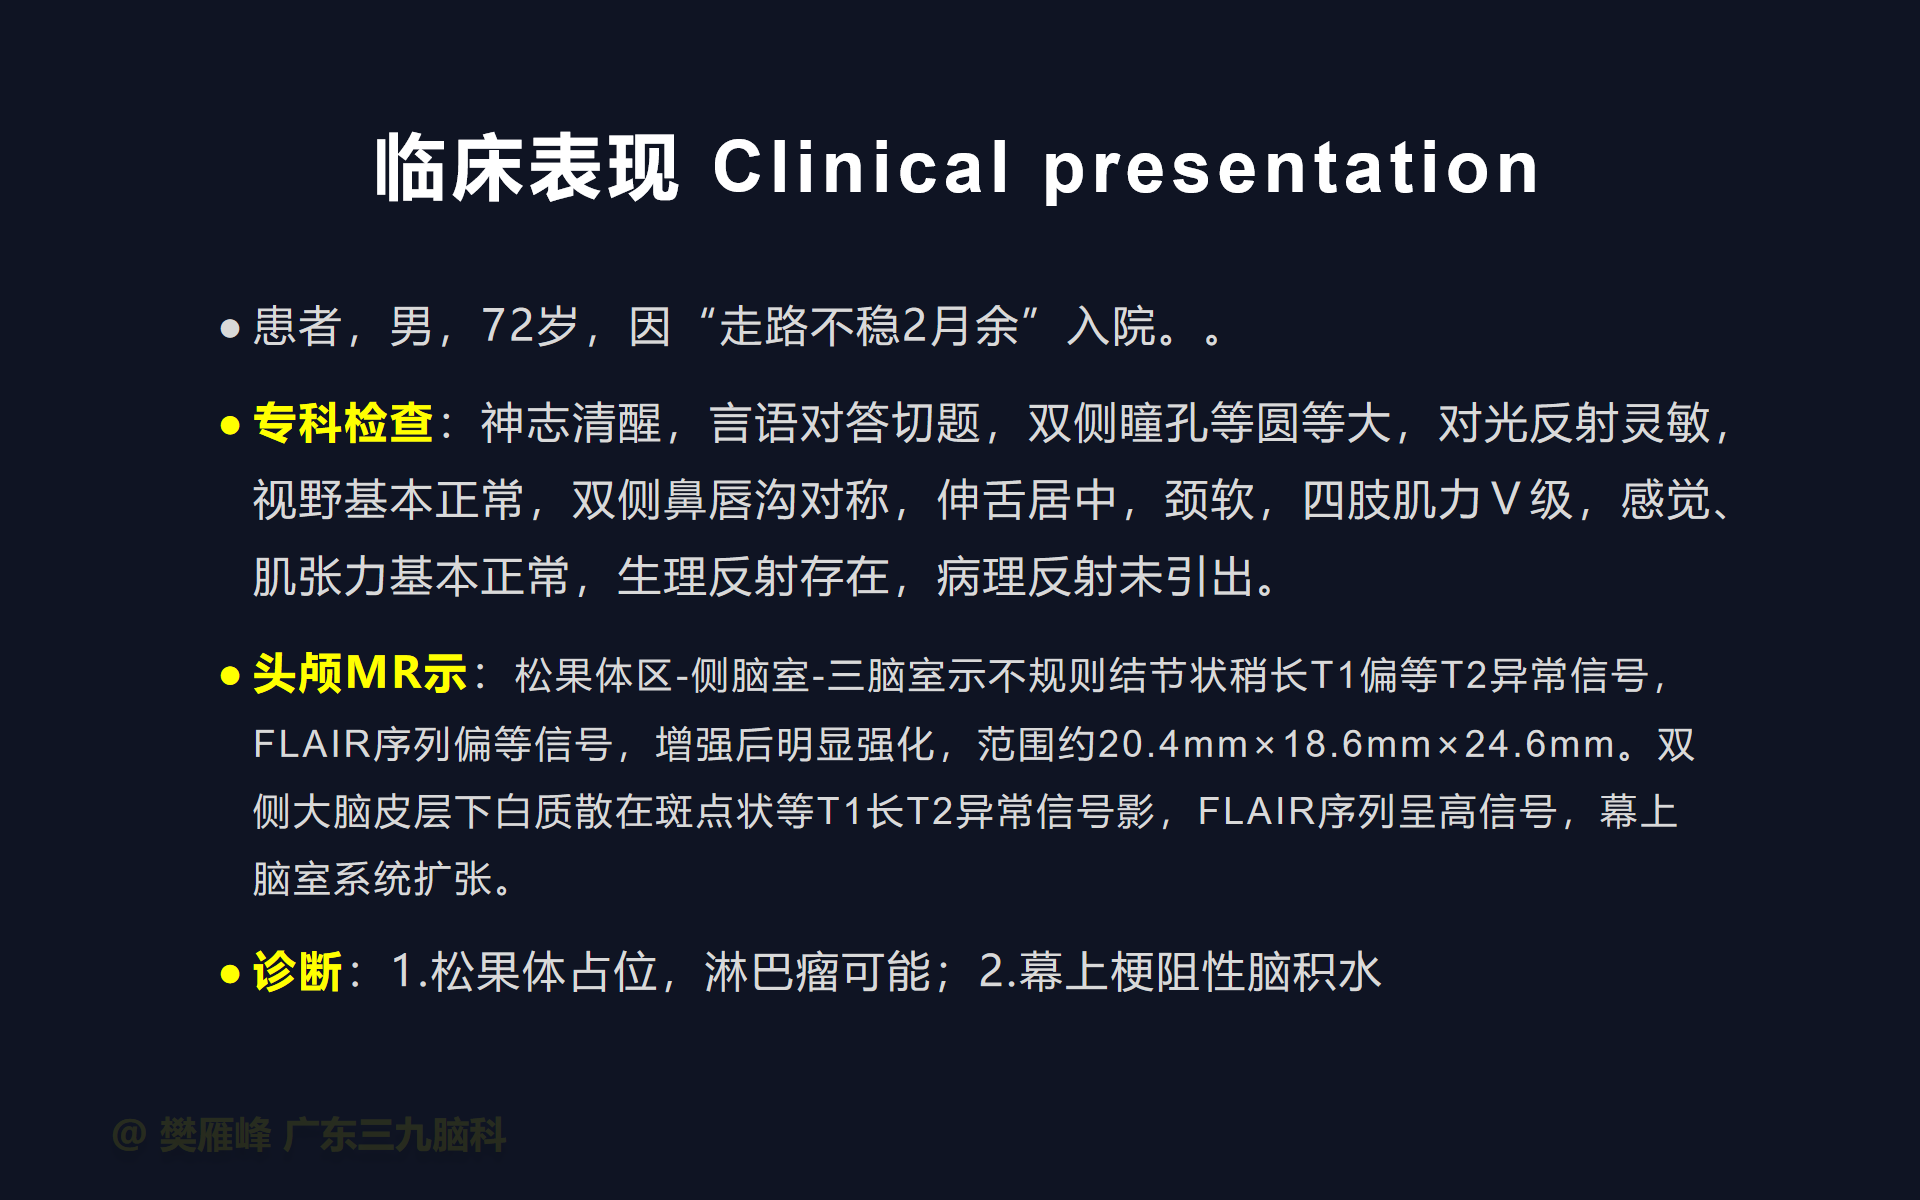

在这个二维手术视频中,展示了2例神经内镜下三脑室底造瘘+活检治疗三脑室后部肿瘤的方法。患者均为三脑室后部病变导致的梗阻性脑积水,病理结果1例为生殖细胞瘤,1例为淋巴瘤,在经过术后的放化疗病情均得到控制,生活质量满意。我们展示了安全的病变活检和第三脑室造瘘的技术要点,以最大限度减少术后继发脑积水和早期并发症。